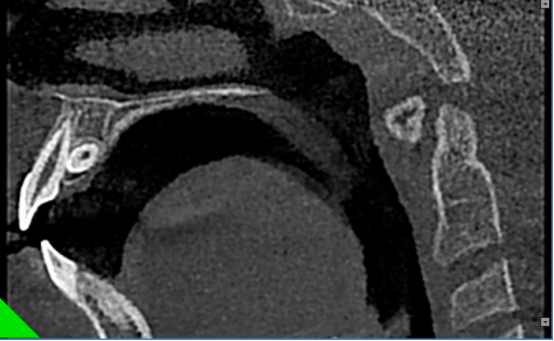

颞下颌关节检查单次扫描即可通过矢状和冠状图像观测到关节间隙的改变和是否发生病理变化。3D影像重建可以清晰提供颞下颌关节、关节头及关节颈部详细解剖信息。